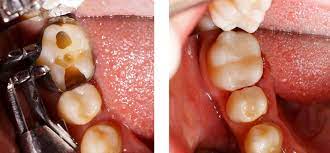

You can read a lot of what I have to say about mercury in dental amalgam fillings. Im well today after suffering with fibromyalgia pains loose teeth and gum disease for decades. Other times the reason for a filling falling out has more to do with further tooth decay happening underneath where the filling was attached.

This can widen the cavity and reduce the strength of the bond holding the filling in. When a composite or an amalgam have decay underneath it can be very difficult to simply replace the filling. Amalgam filling measured 25 microamperes.

The filling may have a cavity under it which is soft and therefore the filling came out because it no longer rested on a solid surface. The filling may have been placed in a situation that a failure is expected. I mean that if a dentist places a filling when a crown is needed then it is asking too much of the filling to hold up the load.